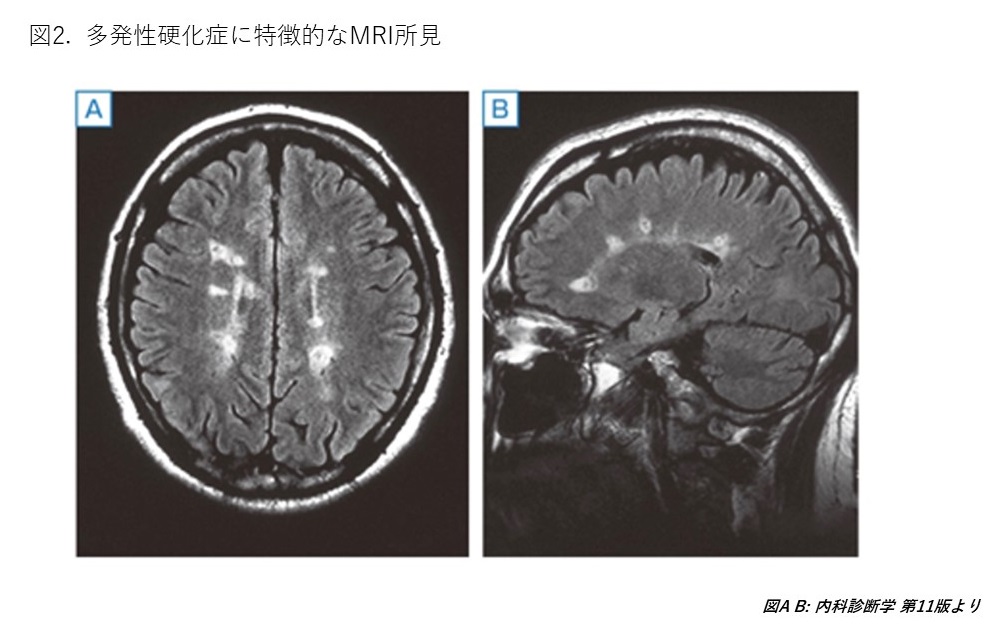

医師紹介 脳神経内科 腎臓・高血圧 呼吸器 循環器内科 消化器・肝臓 糖尿病・内分泌 専門外来 医師紹介 外来医師担当表はこちら 氏名役職診療内容及び専門分野資格水口 英彦参事(坂浜担当診療部長兼任)内科一般呼吸器・身体障害者福祉法第15条指定医(呼吸器機能障害)・協力難病指定医岩下 達雄副院長(感染管理部長兼任)(地域医療支援センター長兼任)(内科担当診療部長事務取扱)(内科部長事務取扱)(脳神経内科部長事務取扱)内科一般脳神経内科・医学博士・日本内科学会 認定内科医・日本神経学会認定 神経内科専門医・指導医・日本認知症学会認定 認知症専門医・指導医・日本頭痛学会認定 頭痛専門医・指導医・日本医師会認定 産業医・日本温泉気候物理医学会認定 温泉療法医・身体障害者福祉法第15条指定医(肢体不自由、平衡機能障害)・難病指定医北川 賢脳神経内科医長内科一般脳神経内科・医学博士・日本内科学会 認定内科医・日本神経学会認定 神経内科専門医・日本神経免疫学会認定 神経免疫診療認定医・日本頭痛学会 会員・日本脳卒中学会 会員・身体障害者福祉法第15条指定医(肢体不自由)・難病指定医柚須 悟循環器内科部長内科一般循環器病学心電図、不整脈・医学博士・日本内科学会 認定内科医・日本循環器学会認定 循環器専門医・臨床研修指導医・「植込み型除細動器(ICD)/ペーシングによる心不全治療(CRT)合同研修」修了証取得・身体障害者福祉法第15条指定医(心臓機能障害)・難病指定医田島 一樹循環器内科医長内科一般循環器・日本内科学会 認定内科医・日本循環器学会認定 循環器専門医・日本医師会認定 産業医・身体障害者福祉法第15条指定医(心臓機能障害)・難病指定医末岡 順介循環器内科医長内科一般循環器・医学博士・日本内科学会 認定内科医石川 啓史循環器内科医長内科一般循環器・医学博士・日本内科学会認定 総合内科専門医・日本循環器学会認定 循環器専門医・日本心血管インターベンション治療学会 認定医・難病指定医瀧 康洋腎臓内科部長内科一般腎臓内科・医学博士・臨床研修指導医・日本内科学会 認定内科医・日本透析医学会認定 透析専門医・日本腎臓学会 認定 腎臓専門医・指導医・身体障害者福祉法第15条指定医(じん臓機能障害)・難病指定医小竹 徹腎臓内科医長内科一般腎臓内科・医学博士・日本内科学会 認定内科医・日本腎臓学会認定 腎臓専門医・日本透析医学会認定 透析専門医・身体障碍者福祉法第15条指定医(じん臓機能障害)・緩和ケア講習会 修了森久保 悟腎臓内科医員内科一般腎臓内科・日本内科学会認定 総合内科専門医・日本腎臓学会 会員鈴木 幹広腎臓内科専修医内科一般腎臓内科竹林 晃一消化器内科部長内科一般消化器・医学博士・日本内科学会認定 総合内科専門医・日本消化器病学会認定 消化器病専門医・指導医・日本消化器内視鏡学会認定 消化器内視鏡専門医・指導医・難病指定医武藤 英知肝臓内科部長(消化器内科担当診療科部長兼任)内科一般消化器・医学博士・日本内科学会認定 総合内科専門医・日本肝臓学会認定 肝臓専門医・日本消化器病学会認定 消化器病専門医・ICD制度協議会認定 インフェクション・コントロールドクター・日本消化器内視鏡学会認定 消化器内視鏡専門医・身体障害者福祉法第15条指定医(肝臓機能障害)・難病指定医原田 耕佑消化器内科医員内科一般消化器藤川 やすえ消化器内科医員内科一般消化器・緩和ケア講習会 修了奥平 玲子呼吸器内科担当呼吸器内科部長内科一般呼吸器・身体障害者福祉法第15条指定医(呼吸器機能障害)・難病指定医・緩和ケア講習会 修了小泉 和正名誉院長内科一般漢方人間ドック外来・医学博士・日本内科学会 認定内科医・日本人間ドック学会 人間ドック認定医・日本人間ドック学会認定 人間ドック健診専門医・指導医・日本東洋医学会認定 漢方専門医・日本医師会認定 産業医・身体障害者福祉法第15条指定医(じん臓機能障害)若林 行雄非常勤医師内科一般物忘れ外来健診・医学博士・日本内科学会 認定内科医・日本神経学会認定 神経内科専門医・日本人間ドック学会 人間ドック認定医・日本医師会認定 産業医・東京都医師会 学校医・身体障害者福祉法第15条指定医(肢体不自由)・難病指定医飯田 崇之非常勤医師内科一般脳神経内科・日本内科学会 認定内科医・日本神経学会認定 神経内科専門医・身体障害者福祉法第15条指定医(肢体不自由)・難病指定医浅川 香織非常勤医師消化器・日本外科学会認定登録医・日本消化器病学会認定 消化器病専門医・日本消化器内視鏡学会認定 消化器内視鏡専門医・日本医師会認定 産業医・緩和ケア講習会 修了宮原 大輔非常勤医師内科一般循環器・日本内科学会 認定内科医・日本内科学会認定 総合内科専門医・日本循環器学会認定 循環器専門医・日本心血管インターベンション治療学会 認定医吉野 鉄大非常勤医師漢方外来・医学博士・日本内科学会認定 総合内科専門医・日本東洋医学会認定 漢方専門医・日本漢方生薬ソムリエ・米国内科学会 上級会員・ECFMG Certificate, STEP3 PASS力石 昭宏非常勤医師腎臓内科・日本内科学会認定 総合内科専門医・日本腎臓学会認定 腎臓専門医・日本透析医学会認定 透析専門医飯田 春信非常勤医師リウマチ・膠原病・日本内科学会 認定内科医・日本リウマチ学会認定 リウマチ専門医・難病指定医佐々木 有紀非常勤医師糖尿病・内分泌・日本内科学会 認定内科医・日本糖尿病学会認定 糖尿病専門医・日本内分泌学会認定 内分泌代謝科専門医村橋 登非常勤医師糖尿病・内分泌広村 宗範非常勤医師糖尿病・内分泌・医学博士・日本内科学会認定 総合内科専門医・指導医・日本糖尿病学会認定 糖尿病専門医・指導医・日本内分泌学会認定 内分泌代謝科専門医・指導医・日本内分泌学会 評議員・内分泌代謝領域専門研修指導医・糖尿病内科領域専門研修指導医・日本抗加齢医学会 評議員・臨床研修指導医・日本糖尿病学会 所属・日本内分泌学会 所属・日本内科学会 所属・日本甲状腺学会 所属・日本抗加齢学会 所属稲葉 亮非常勤医師内科一般脳神経内科・日本内科学会 所属・日本神経学会 所属・日本内科学会 JMECC・日本救急学会 ICLS木塚 裕太非常勤医師内科一般脳神経内科・日本内科学会認定 総合内科専門医・日本内科学会 JMECC・緩和ケア講習会 修了・日本神経学会 所属・日本認知症学会 所属・日本脳神経血管内治療学会 所属岡田 浩太郎非常勤医師内科一般脳神経内科・日本内科学会 所属・日本神経学会 所属吉田 昇悟非常勤医師内科一般脳神経内科・日本内科学会 所属・日本神経学会 所属光石 彬史非常勤医師呼吸器内科・日本内科学会 認定内科医・指導医・日本呼吸器学会認定 呼吸器専門医・緩和ケア講習会 修了 脳神経内科 診療内容 脳神経内科では、脳梗塞、脳出血、認知症、頭痛、てんかん、Parkinson病などの日常生活で多く遭遇するご病気の他、多発性硬化症、視神経脊髄炎スペクトラム障害、重症筋無力症などの神経免疫疾患の診療も行っています。 当院では、多発性硬化症(Multiple sclerosis; MS)や視神経脊髄炎スペクトラム障害(Neuromyelitis optica spectrum disorder; NMOSD)に対する最新の治療を行うことが可能なことが特色のひとつです。それぞれのご病気の特徴を紹介いたします。 外来診察室 多発性硬化症(MS) 1.特徴 中枢神経系(脳・脊髄・視神経)において、空間的・時間的に病巣が多発する原因不明の脱髄疾患です。「空間的・時間的多発」とは、「中枢神経系で場所を変えて再発する」、「1か月以上の間隔をあけて再発する」ということを意味しており、MSの特徴のひとつです。「脱髄」とは、中枢神経系の神経線維の構成成分である軸索とそれを覆う髄鞘のうち、主に「髄鞘が障害される」ことを言います。病態の機序としては、ご自身の免疫細胞の異常(自己免疫)が重要であると考えられており、近年は環境要因や遺伝的要因、EBウイルス感染などの関与も指摘されていますが、未だ明確な原因は不明です。2.典型的な臨床経過 神経障害の再発や寛解に続き、病状が進行していくことが知られています。①再発期は、急激な臨床徴候の増悪を引き起こします。②寛解期には、しばしば病状の改善が不完全であり、段階的な症状の進行につながる可能性があります。③進行期には、歩行能力が徐々に失われていくことが知られています。無治療では、約80%が進行すると考えられています(図1)。 3.自覚症状 主要な自覚症状は表1の通りとなります。 4.診断方法1) 血液検査 MSと似た疾患は多数あります。肝臓、腎臓、骨髄の働きや、感染症の有無、電解質異常、ホルモン異常、自己抗体、腫瘍マーカーの検出の有無などを調べ、他の疾患の可能性が否定的であることを確認します。2) 脳脊髄液検査 脳や脊髄の周りにある脳脊髄液の性状から、中枢神経系の炎症の有無を間接的に評価する検査です。髄液中の細胞数、タンパクの量や内容、免疫グロブリン産生の状態を調べます。3) MRI MSの特徴である「空間的多発性」を評価します(図2)。 特徴的所見が異なる領域に複数みられることを確認します。 5.治療法 MSの治療では、病気が悪くなった時(再発期)と症状が落ち着いている時(寛解期)とで治療法が変わります(表2)。 視神経脊髄炎スペクトラム障害(NMOSD) 1.特徴 NMOSDは、中枢神経系(脳・脊髄・視神経)において高度な炎症と強い組織障害を認める自己免疫性疾患です。病態は、自身の免疫を担うB細胞によって産生された抗AQP4抗体が、抗体依存性・細胞介在性または補体依存性に、血液脳関門におけるアストロサイトを障害することで発病すると考えられています。先述のMSとは異なる疾患と考えられており、重篤で治療抵抗性の神経症状を呈することが特徴的です。ここでは、MSと比較しながら解説していきます。2.典型的な臨床経過 MSは、再発や寛解を繰り返しながら徐々に神経障害が進行していくことが特徴的でした。NMOSDは、重篤な神経障害を来しやすく、発症や再発の度に重篤な神経障害を残しやすいという特徴があります(図3)。 3.自覚症状 MSと比較して、目の症状は両側に出やすく、脊髄の障害は広域に起こりやすい傾向にあります。吃逆(しゃっくり)などもNMOSDでより特徴的となる症状です。4.診断方法 MSと同様、血液検査、脳脊髄液検査、MRI検査を行って診断していきます。NMOSDでは、血液検査で抗AQP4抗体陽性となる場合、従来からの免疫抑制薬よりも高い治療効果が期待できる生物学的製剤が使用可能となるため、抗AQP4抗体の測定は大変重要な検査です。5.治療法 ご病状が悪くなった時(急性期)と、ご病状の悪化が止まった時(慢性期)とで、治療方法が異なります。 急性期は、ステロイドパルス療法、血漿交換療法が主体であり、視神経で炎症を来した場合は免疫グロブリン療法も可能です。ただし、発症から時間が経過すると有効性が大きく低下することから、重症例では早期に血漿交換療法を行うことが重要です。 慢性期は、次の再発を予防するための治療を行う必要があります。抗AQP4抗体陽性例では、本邦では生物学的製剤5剤が使用可能であり、従来薬であるコルチコステロイドや免疫抑制薬よりも高い治療効果が期待されています。近年は、「再発ゼロ、ステロイドゼロ」を目指すことが目標とされており、生物学的製剤を積極的に選択する根拠となり得ます(表3)。 主な説明はこちらに記載した通りとなります。 眼の症状の評価は眼科と、血漿交換療法は腎臓内科と連携し、診療を行います。 ご自身の症状に不安がある場合や、現在、既に治療中であっても今後の方針について相談したい場合など、木曜に免疫外来を行っておりますので、いつでもご相談ください。 検査内容 MRI・MRA検査 / CTスキャン / 脳波検査 / 神経伝導速度 / 筋電図 / 聴性脳幹誘発電位検査 / 髄液検査 腎臓・高血圧 詳しくは腎臓内科のページをご覧ください。 腎臓内科 呼吸器 喘息、気胸、各種炎症性肺疾患、肺がんなどの治療にあたっています。さらに、急性呼吸不全に対しては、特別な病室(HCU)で、厳重な心肺監視装置によるモニタリングのもとで、集学的な治療がおこなわれています。また、肺気腫や慢性気管支炎などによる慢性呼吸不全に対しては、在宅酸素療法をおこない良好な治療効果をあげています。 呼吸機能検査 検査内容 呼吸機能検査・気道過敏検査 / 胸部CT・MRI検査 / 気管支鏡検査 / 経気管支肺生検(TBLB) / 穿刺針生検 / 訪問看護・在宅酸素療法 循環器内科 狭心症、心筋梗塞、心筋症、急性・慢性心不全、不整脈などの心疾患の検査・治療を行っています。 急性期の心臓疾患に対して、可能な限り対応をしております。 2016年4月に血管撮影装置や検査周辺機器の更新が終了し、検査施行が不可能であった冠動脈造影術やステント留置による冠動脈形成術を再開することができ、現在まで合併症なく症例を増やしてきました。 また最近の循環器疾患の症例は多様化、高齢化しており、併発症がたくさんある循環器症例が多くなってきました。 当院の内科には心臓だけでなく、呼吸器、糖尿病、腎臓、神経の専門医がスタッフでおりますので、一丸となって病気に対応することができる状況にあります。 しかし当院では治療の完結ができない症例・病態もありますので、その際には近隣の大学病院、 CCUを有する病院へ速やかに紹介しております。 また虚血性心疾患だけではなく、突然死予知指標検査、徐脈性不整脈や頻脈性不整脈の電気生理学的検査などを行うことで、ペースメーカの植込み・電池交換、心房粗動や上室性頻拍症(PSVT、頻脈発作を伴ったWPW症候群)などのアブレーションも行なっています。 高齢化とともに増えている疾患に心不全があります。 当院では心不全教育入院のクリニカルパスを活用して、心不全を発症する前の「隠れ心不全」の状態から治療を介入する目的で、治療だけではなく、予防含めた患者教育にも力を入れています。 血管撮影装置 ペースメーカ植え込み後 検査・治療 標準12誘導心電図、24時間ホルター心電図、突然死予知指標検査、24時間自動血圧測定、起立性調節障害検査、運動負荷心電図、心臓超音波検査(心エコー)、心臓CT(冠動脈CT)、大血管CT・MRI、電気生理学的検査、ペースメーカ植込み術・電池交換、カテーテル心筋焼灼術(アブレーション)、冠動脈造影検査・冠動脈形成術 消化器・肝臓 食道、胃、十二指腸、小腸、大腸のすべての消化管と、肝臓、膵臓、胆嚢、胆管などの腹部諸臓器の疾患に対して診療を行っています。非常に幅広い分野ですが、患者さんの治療と検査がスムーズにおこなえるように、外科医師との間で協力しあいながら診療をおこなっています。 内視鏡室 検査内容 上部および下部消化管造影検 / 胃内視鏡検査 / 大腸内視鏡検査 / 腹部超音波検査 / 腹部CT・MRI検査 / 経皮経肝胆道造影検査(PTC) / 内視鏡的逆行性胆管膵管造影検査(ERCP) / 腹部血管造影検査 / 肝生検検査 糖尿病・内分泌 糖尿病、甲状腺疾患、副腎疾患などの治療にあたっています。糖尿病は早期発見・早期治療により、重篤な合併症を予防することが大切です。このため当院では栄養士による食事指導やリハビリテーション科による運動療法にも力を入れています。また、糖尿病患者さんは、末梢神経障害、腎障害、網膜症、虚血性心疾患などと合併症を来たすことがあります。その予防と治療のため、各科専門領域の医師と連携し治療にあたっています。 栄養指導 検査内容 糖尿病食栄養指導 / 糖尿病教室 / 血糖自己測定 / インスリン自己注射 / 糖負荷試験 / 神経伝導速度 / 心電図R-R間隔変動係数測定(CV-RR) その他、血液疾患(貧血、血漿板減少症、骨髄腫、リンパ腫など)やリウマチ、膠原病(SLE、強皮症、皮膚筋炎など)に対しても診療をおこなっていますが、重症例や高度の専門性を要する疾患(白血病など)については、診断がついた時点で大学病院などに紹介しています。 専門外来 専門外来はこちら